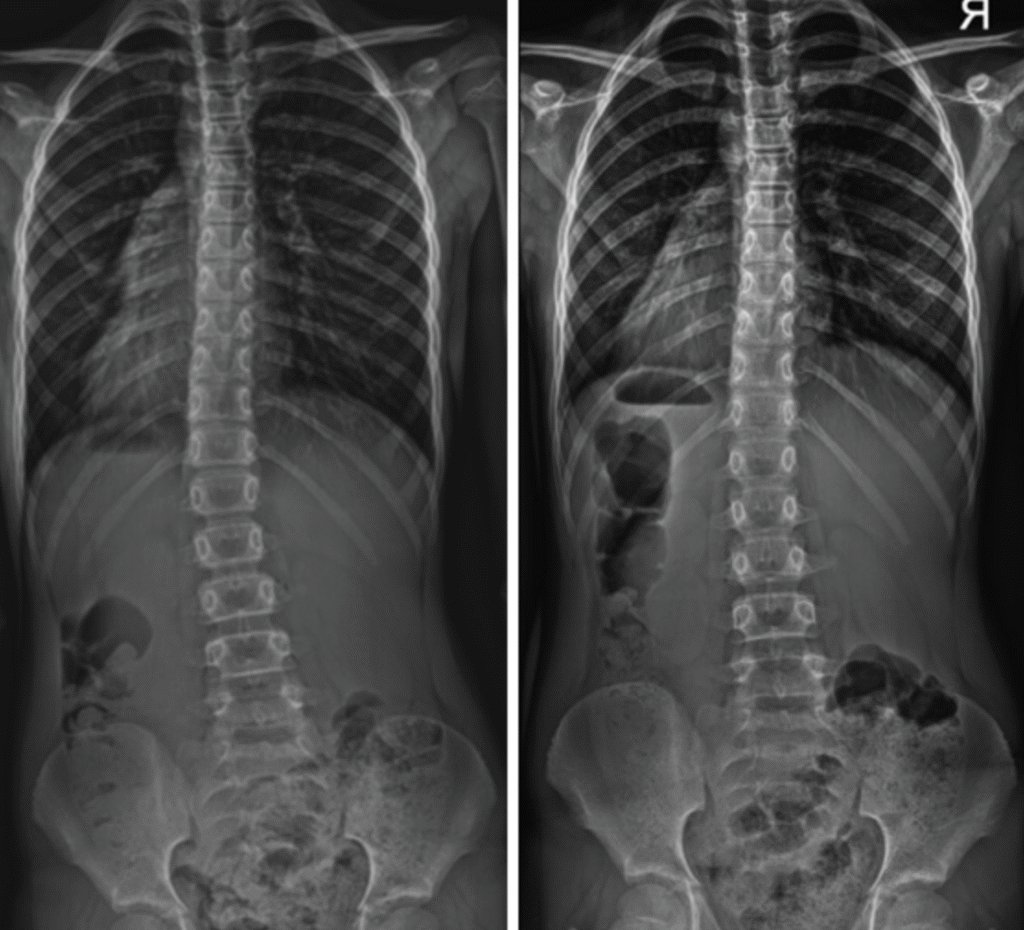

Gabriela – 18 lat

Terapia prowadzona w okresie 20.02 – 04.09.2018 (30 zabiegów) Częstotliwość zajęć – 18 zabiegów 2 x tydz., 12 zabiegów 1 x tydz.